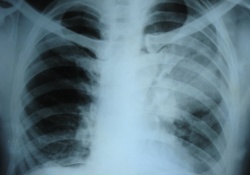

Туберкулёз – это инфекционное заболевание, которое вызывается возбудителем – микобактериями туберкулёза (Mycobacterium tuberculosis), и характеризуется образованием специфических гранулём в разных органах и тканях.

Вирус иммунодефицита человека (ВИЧ) является наиболее сильным из всех известных факторов риска, способствующих активации латентной туберкулезной инфекции.

Согласно заявлению ВОЗ, в настоящее время уровень смертности от туберкулеза является сопоставимым с показателями смертности от СПИД, что вернуло некогда побежденную болезнь в число главных «убийц» жителей планеты. Такое положение вещей неприемлемо.

Остались в прошлом те времена, когда медики всего мира триумфально сообщали о практически полной победе над туберкулезом. Возбудитель смертельно опасного недуга взял таймаут, перегруппировал свои силы и теперь уверенно шагает по странам Старого Света.